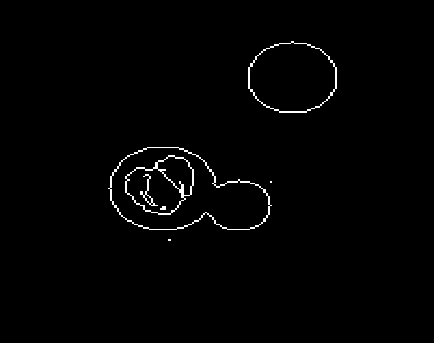

For this experiment, we used a modified phantom image that is shown in Figure 4(a). In contrast to the previously used phantom, this image includes also weaker edges that are more challenging to detect. For this phantom, we generated CT data using the same sampling scheme as in our first experiment (Section 4.1) and computed the LoG-feature maps fULoG𝑓subscript𝑈LoGf\circledast U_{\rm LoG} using the FBP approach (cf. Figure 4(b)) and using our approach (cf. Figure 4(c)) with μ=0𝜇0\mu=0, λ=0.002𝜆0.002\lambda=0.002, and 100100100 iterations of the FISTA algorithm for (4.1). Subsequently, we generated corresponding binary edge maps by extracting the zero crossings of these LoG-feature maps (cf. Figure 4(d) and 4(e)) by using the MATLABs edge functions. Note that this procedure is one of the standard edge detection algorithm, known as the LoG edge detector, cf. [20]. For both methods, we took standard deviation α=1.3𝛼1.3\alpha=1.3 for the application of the Gaussian smoothing and threshold t=0.005𝑡0.005t=0.005 for the detection of the zero crossings. As can be clearly seen from the results, the edge detection based on our approach (cf. Figure 4(d)) is able to detect also the weaker edges inside the large disc. In contrast, edge detection in combination with FBP-LoG featuremap was not able to detect the edge set correctly due to strong undersampling artefacts.

Refer to caption

Figure 4.4: LoG edge detection. The modified phantom image (4(a)) includes also weaker edges that are more challenging to detect. Subfigures (4(b)) and (4(c)) show reconstructions of the LoG feature maps, that were generated using the FBP algorithm and our approach, respectively. The corresponding binary edge masks generated by the LoG edge detector are shown in (4(d)) and (4(e)).